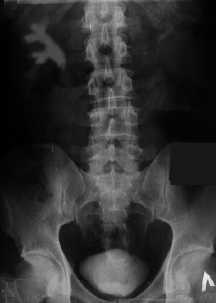

9. Внутривенная экскреторная урография. Для диагностики пиелонефрита большое значение имеет рентгеновское исследование мочевыводящих путей с применением контрастного вещества. Показаниями к проведению внутривенной урографии являются первая инфекция мочевых путей у мужчин и повторные инфекции у женщин, постоянная микро- и макрогематурия, лихорадка. В ходе урографии определяют строение мочевыводящих путей и врожденные аномалии их развития, устанавливают возможную причину пиелонефрита (например, может иметь место закупорка мочеточника или лоханки камнем). Контрастная рентгенография мочевыводящих путей позволяет узнать давность существования болезни, ее стадию, степень нарушения уродинамики. За 12-24 часа до исследования проводят пробу на чувствительность к контрастному веществу. Если появились кожный зуд, аллергический насморк, слезотечение, головная боль, тошнота или рвота, введение контраста противопоказано. Тогда в целях диагностики проводят ультразвуковое исследование. В день исследования делают очистительную клизму и дают активированный уголь. Эти мероприятия необходимы для освобождения кишечника от каловых масс и газа, снижающих качество снимков. По этой же причине до исследования не рекомендуется есть. В рентгеновском кабинете вводят контрастное вещество и через определенные промежутки времени делают снимки почек и нижних мочевых путей.